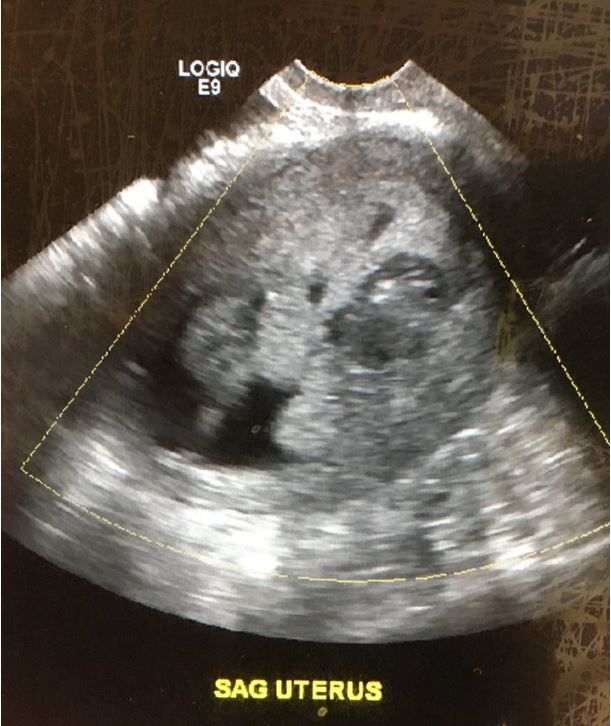

The patient is 42-years-old, G2P1 and presents with 1 week of vaginal spotting, 4 days of pelvic pain. Review the ultrasound and lab findings. What's your diagnosis?

Patient history. A 42-year-old woman who is G2P1 and approximately 6 weeks pregnant is sent from her clinic to the emergency department for 1 week of vaginal spotting and 4 days of pelvic pain. She denies any fever, dysuria, vomiting, or other complaints.

Molar Pregnancy fromThe Emergency Medicine 1-Minute Consult Pocketbook